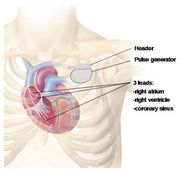

| 22:23, 5 August 2012 | Schematic.jpg (file) |  |

54 KB | 1 | |

| 22:47, 5 August 2012 | Schematicpic.jpg (file) |  |

53 KB | 2 | |